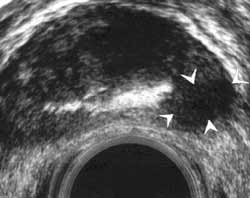

Рис. 15. Трансректальная эхограмма. Рак предстательной  железы. Гипоэхогенный узел.